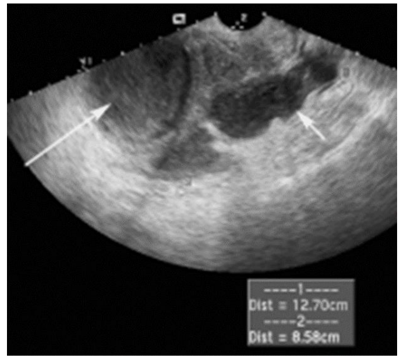

Mulher de 21 anos de idade, sem comorbidades prévias, procura atendimento em unidade de emergência por quadro de dor pélvica há 2 dias. A dor é localizada em quadrantes inferiores do abdome, sendo descrita como uma cólica de intensidade moderada (5/10), sendo mais intensa à esquerda. Além disso, apresentou febre, náuseas e um corrimento genital amarelado no mesmo período. Nega outros sintomas gastrointestinais ou urinários. Ela notou que os sintomas começaram após ter tido algumas relações sexuais desprotegidas na última semana. Tem vida sexual ativa, sem parceiro fixo e com uso irregular de condom. Tem história prévia de uma gestação, com parto normal sem complicações há 2 anos. Desde então, vem em uso de dispositivo intrauterino (DIU) de cobre, sendo que a última menstruação ocorreu há cerca de 10 dias. Ao exame, apresentou febre (Tax = 38,6ºC), PA 110x70mmHg e FC 96 bpm. O abdome é doloroso à palpação em quadrantes inferiores, sem dor à descompressão brusca. Ao toque vaginal, apresenta útero em anteversoflexão, de tamanho, consistência e mobilidade normais. O colo uterino é fibroelástico e doloroso à mobilização, com anexo esquerdo doloroso à palpação e anexo direito não palpável. Ao exame especular, foi vista saída de secreção purulenta do orifício externo do colo uterino, sendo visualizados fios do DIU de aproximadamente 2cm. Foi feita uma ultrassonografia point-of-care, cuja imagem da região anexial esquerda pode ser vista na imagem a seguir (página ao lado):

Qual é o diagnóstico e o tratamento que devem ser feitos neste momento?